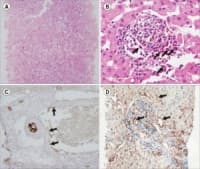

Реакция на отхвърляне на трансплантата

Имунният отговор към трансплантирания орган се състои както от клетъчни (медиирани от лимфоцити), та...